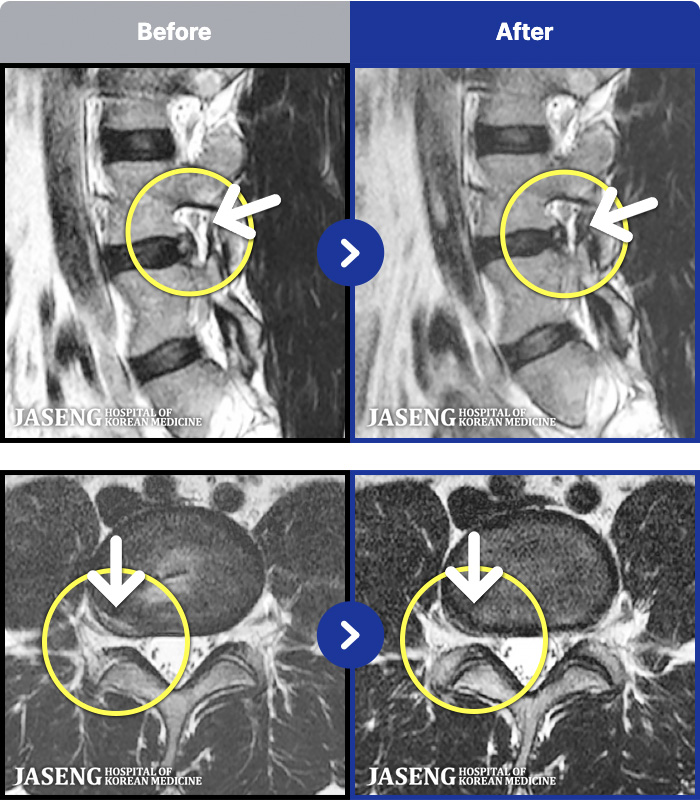

MRI ġ

1,299 MRI ũ ʸ Ȯϼ.